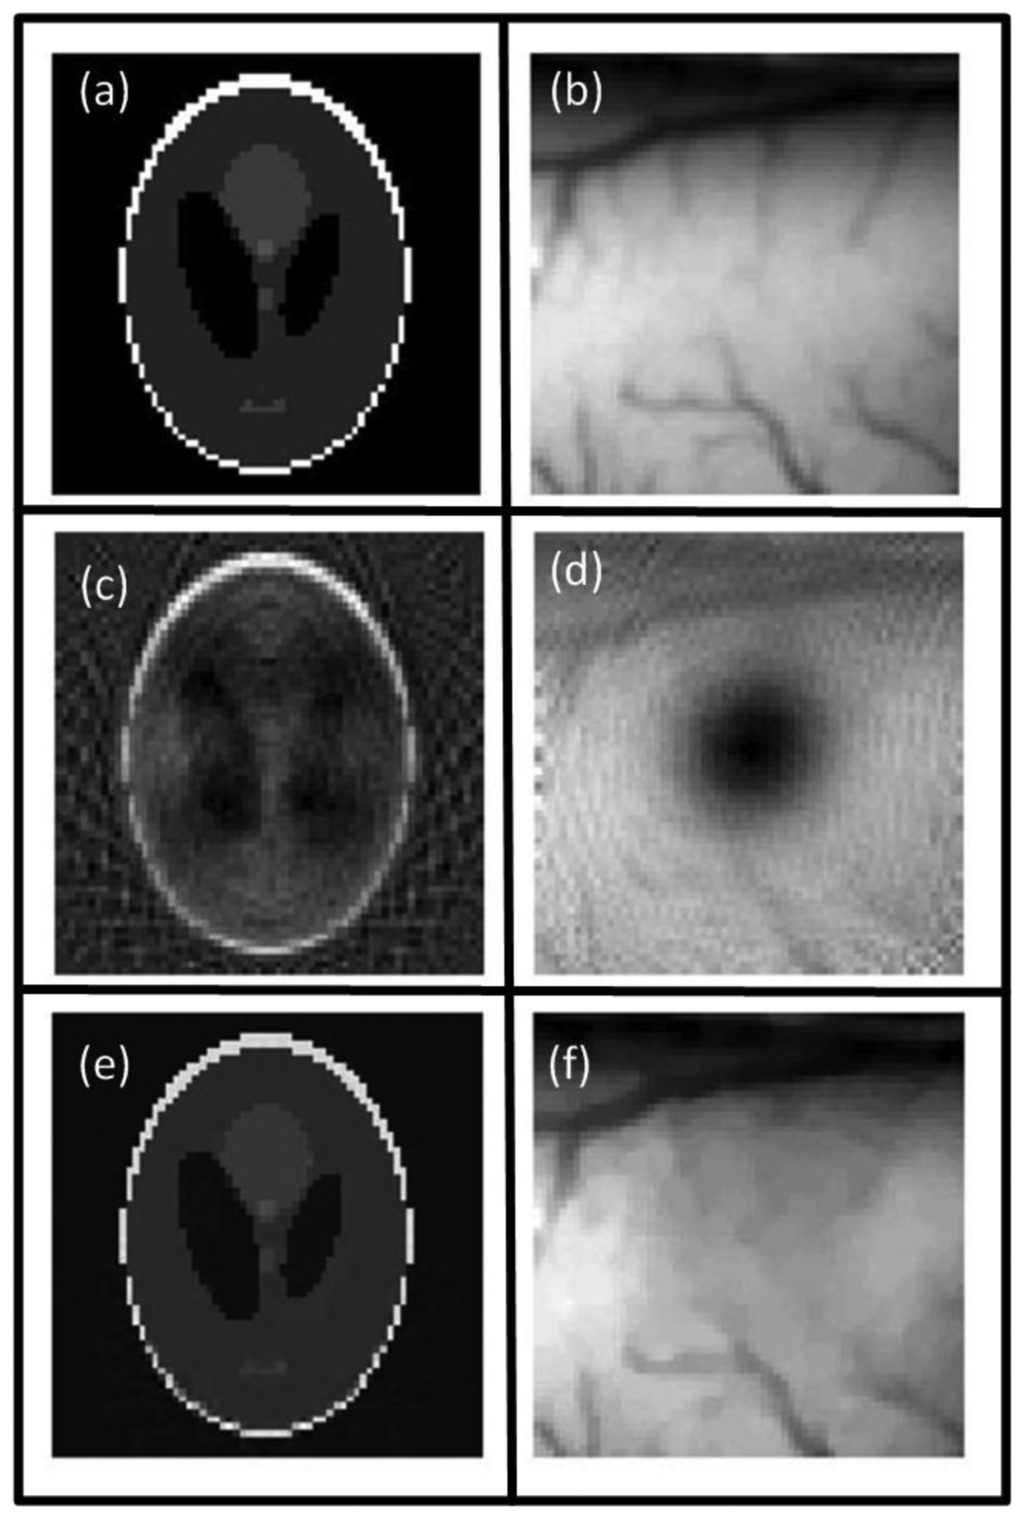

In media with heterogeneous acoustic properties, scattering and reflection of the acoustic waves may occur at boundaries of highly mismatching media. Examples include bones or air cavities such as the lung. Wang et al. studied the effects of reflection at soft and hard boundaries and were able to considerably improve image quality in the presence of reflections at planar boundaries [111], which might however not always be applicable to realistic imaging scenarios. Anastasio et al. showed that tomographic OA signals, acquired from multiple view angles (projections), contain complementary information thus images can be equally reconstructed from truncated signals, which may improve image quality in heterogeneous acoustic media due to data redundancy principles [112]. Dean-Ben et al. presented a statistically weighted BP algorithm that efficiently accounted for strong acoustic reflections [113,114]. The algorithm weights each detected signal by a factor that represents the probability of the signal being undisturbed during propagation. In this way, reconstruction artifacts arising from scattering can be suppressed (Figure 5).

where Ψ0 is the representation of the image in the CS basis and λ is a scalar regularization parameter. Equation (11) can be solved by nonlinear minimization methods, which typically require longer calculation times as compared to just solving Equation (9). In comparison to standard image reconstruction methods, CS approaches have further shown reduction of artifacts in images when reconstructing from only a few tomographic projections (Figure 7). Thus, by reducing the number of acquired projections, these approaches hold great promise for dramatic reduction of image acquisition and reconstruction times as well as instrumentation costs.